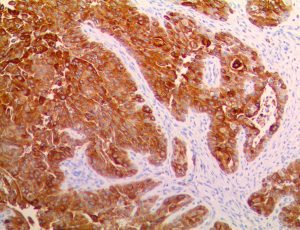

It is the ICU physician who is most likely to witness one of the deadliest manifestations of the abnormal immunological response, the cytokine storm syndrome (CSS). This response is also referred to by some as the cytokine release syndrome (CRS). CSS is characterized by continuous activation and expansion of macrophage and lymphocyte populations, which secrete large amounts of cytokines, causing the cytokine storm. This massive cytokine release is akin to hemophagocytic lymphohistiocytosis (HLH) disease, a syndrome characterized by initial unchecked and persistent activation of cytotoxic T lymphocytes and NK cells.

Clinical and laboratory manifestations of HLH include fever, enlarged liver and/or spleen, neurologic dysfunction, coagulopathy, liver dysfunction, cytopenias (i.e., low levels of erythrocytes, leukocytes, and/or platelets), hypertriglyceridemia, hyperferritinemia, hemophagocytosis, and eventually diminished NK cell activity as the immune system becomes progressively paralyzed. HLH can be familial (primary HLH) or secondary to another disease process (sHLH), such as rheumatic disease, in which it is referred to as macrophage activation syndrome (MAS, characterized by elevated ferritin).

This activation induces inflammatory monocytes to highly express IL-6, starting a localized and then systemic cascade effect that results in hyperproduction of IL-6, which accelerates the inflammatory process. Because IL-6 also increases vascular permeability, excessive levels cause blood vessels to become very leaky. This, along with clotting factors released from vascular endothelial cells, stimulates the coagulation cascade, resulting in microthrombosis (tiny clots), which leads to ischemia and tissue death of the kidney, intestines, heart, liver, brain and extremities.